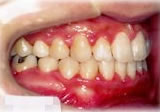

反対咬合(受け口)症例

初診時年齢24歳6ヶ月。前歯部反対咬合を主訴に来院。

骨格性反対咬合と診断し、外科的処置を併用して治療。

右側面 右側面 右側面